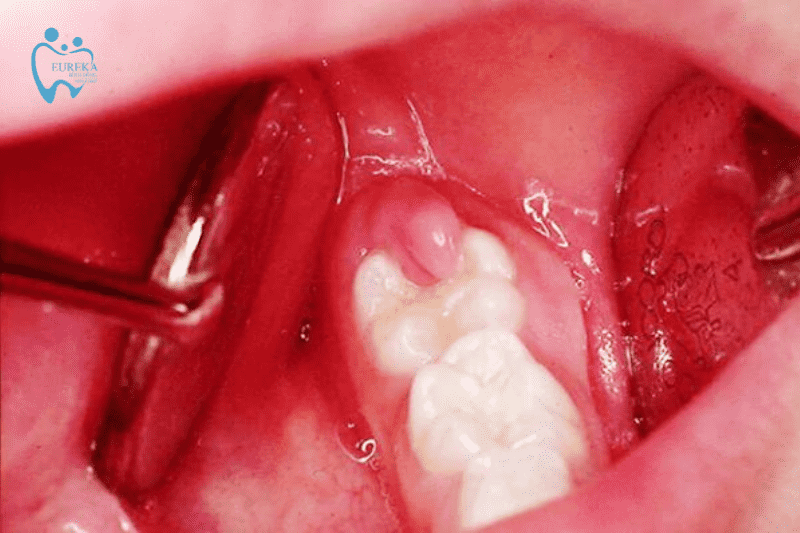

- Phần lợi của người bệnh bị sưng phồng lên ở chính chỗ mọc răng khôn, có màu đỏ.

- Một số trường hợp lợi sẽ chảy dịch mủ ra khi ấn vào.

- Người bệnh sẽ gặp khó khăn trong việc ăn uống, giao tiếp, ngay cả khi há miệng cũng sẽ cảm thấy đau đớn và khó khăn. Viêm lợi trùm có thể gây ra nhiều bất tiện trong quá trình sinh hoạt và làm việc của bệnh nhân.